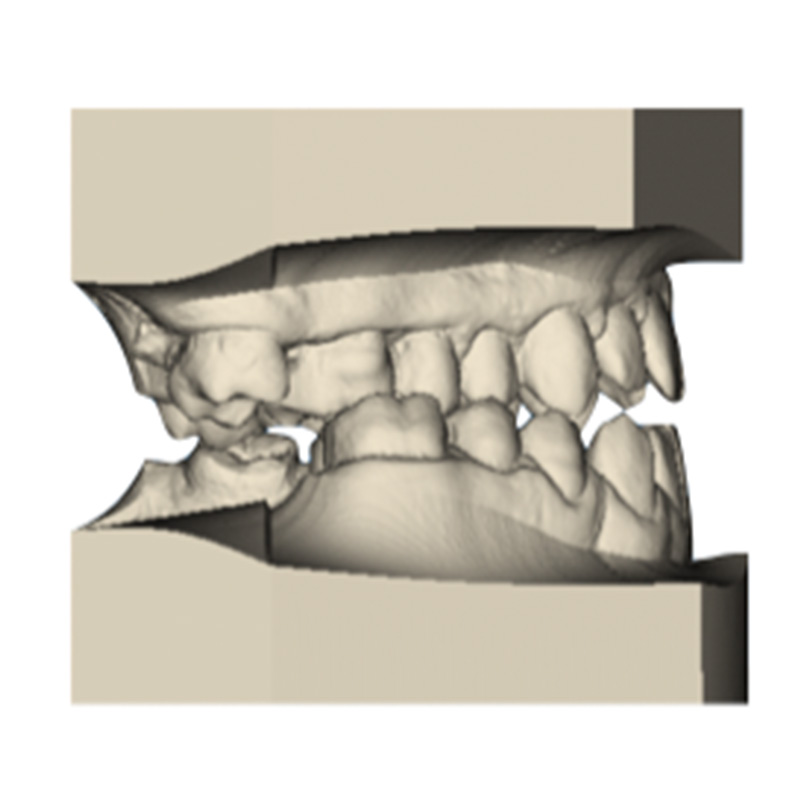

Once the transverse discrepancy was corrected, treatment continued with Spark Aligners to address the vertical plane. The planned vertical correction involved extruding the upper anterior teeth, with 1.7 mm of extrusion in the upper arch, and 1.5 mm in the lower arch using attachments. To assist in bite closure, turbo bites were employed to intrude the mandibular molars.

As shown in the accompanying images, the planned vertical correction was fully achieved. At this stage, provisional composite veneers were placed from canine to canine in the upper arch to enhance the patient’s aesthetics and compensate for Bolton’s discrepancy.

For sagittal correction, a new set of aligners made from Trugen XR™ material was fabricated. The corono-distal tipping of the premolars in the fourth quadrant was corrected using intermaxillary elastics.

Ultimately, we successfully corrected the crossbite, open bite, and Class III canine relationship. The patient rehabilitated tooth #26 with an on lay and tooth #47 with an implant, resulting in a stable occlusion. Post-treatment retention involved a fixed retainer in the lower arch and removable retainers for both upper and lower arches to maintain the treatment results.